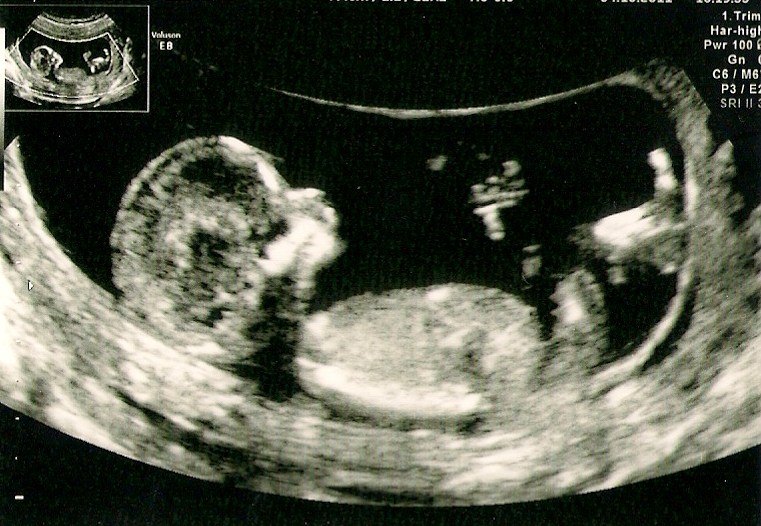

jeg har idag været til NF og den gik godt... det har jeg jo ikke prøvet før..... fik en risiko der hed 1:9965 og det må jeg jo bestemt ikke klage over......og der var fuld gang i den lille spire... så nu tør jeg vidst omsider tro på det lykkes denne gang...... godt nok er omstændighederne noget anderledes end sidste gang.. da var jeg stadig kærester med barnets far....... men vi udelukker ikke at vi en dag blir kærester igen....... men ikke lige nu........

så her er et billede af min lille 6cm baby :-)